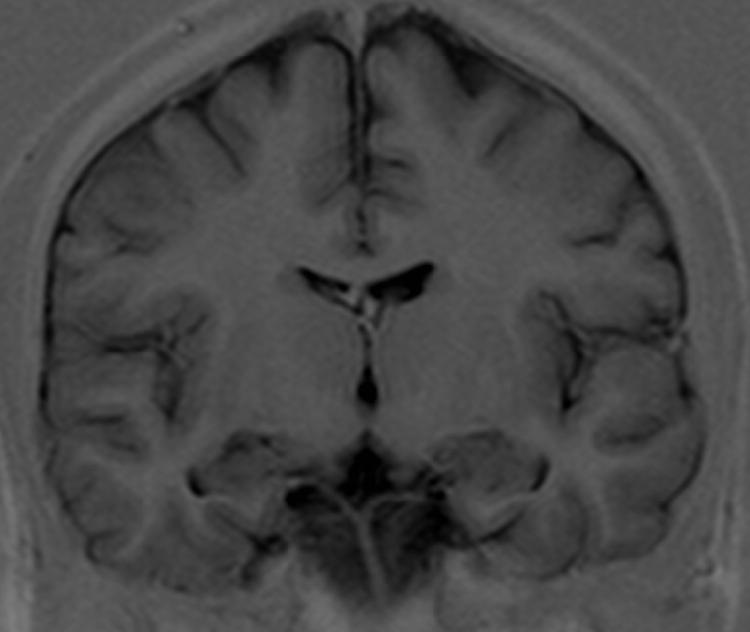

| Corpus callosum - truncus |

| Septum pellucidum |

| Fornix - corpus |

| Thalamus |

| Adhesio interthalamica |

| Nucleus subthalamicus |

| Nucleus caudatus - corpus |

| Putamen |

| Globus pallidus |

| Claustrum |

| Capsula interna - crus posterior |

| Ventriculus lateralis - pars centralis |

| Ventriculus lateralis - cornu temporale |

| Nucleus caudatus - cauda |

| Ventriculus tertius |

| Substantia nigra |

| Fossa interpeduncularis |

| Crus cerebri |

| Pars basilaris pontis |

| Pyramis medullae oblongate |

| Hippocampus |

| Sulcus lateralis (Sylvii) |